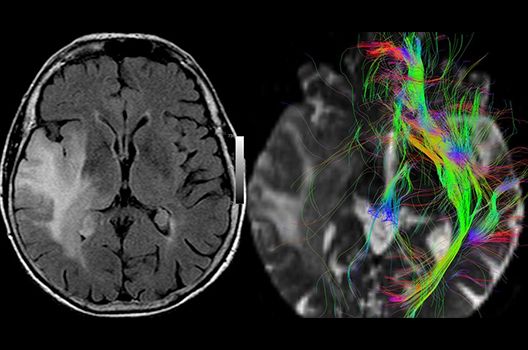

- MR-Diffusionstensorbildgebung (Faserbahndarstellung/fiber tracking)

Die Schwerpunkte in der MR-Forschung liegen in der multiparametrischen und funktionellen Bildgebung bei onkologischen und anderen, neuroradiologischen Fragestellungen und umfassen die Anwendung modernster MR-Verfahren sowie die Untersuchung an Hochfeld-Geräten.

Die Magnetresonanztomographie (MRT) ist ein Verfahren, bei dem durch magnetische Kräfte Bilder des Körperinneren angefertigt werden. In der Neuroradiologie können manchmal kleinste Veränderungen schwere Folgen haben; daher forschen wir an der Entwicklung hochauflösender MRT-Sequenzen, mit denen diese Prozesse und auch einzelne Nervenfaserbahnen sichtbar gemacht werden können. Darüber hinaus sind bei vielen Erkrankungen des Gehirns die Blutgefäße betroffen. Daher arbeiten wir an der Neu- und Weiterentwicklung von MRT-Sequenzen zur Darstellung der Blutgefäße und zur Blutflussanalyse (sog. „Angio-MRT“). Einen besonderen Forschungsschwerpunkt unserer Klinik stellen die MR-Protonenspektroskopie und die funktionelle MRT dar, mit denen die Analyse einzelner chemischer Substanzen im Hirngewebe oder die Darstellung ausgewählter Hirnfunktionen möglich ist.